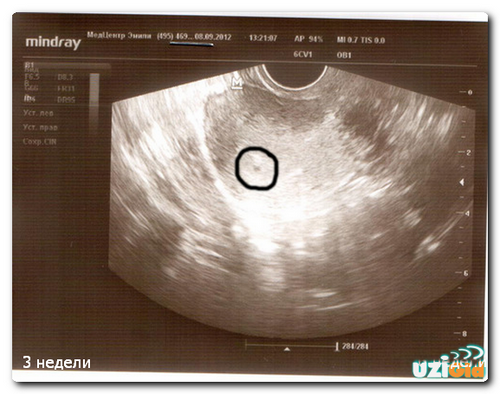

УЗД на 1 тижні вагітності

Фахівці не призначають УЗД під час першого тижня вагітності, так як сам факт зміни положення жінки ще не підтверджений. Жінка навіть не буде здогадуватися про такому маленькому терміні. Про вагітність як про становище говорять вже після 3-го тижня і УЗД може її підтвердити починаючи з цього терміну.

При відчутті деяких змін в організмі, можна звернутися до лікаря-гінеколога для призначення УЗД. На такому терміні УЗД вже здатна підтвердити наявність плода всередині матки.